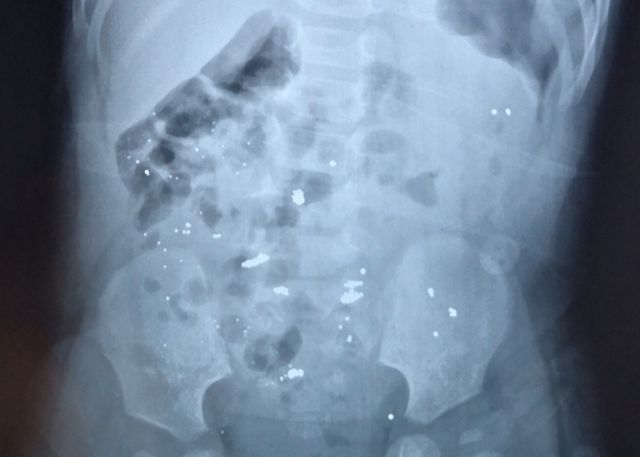

因为水银密度比较大,堆积在体内易造成肠穿孔,要让孩子少活动。一般24小时内,水银就会通过大便自然排出。如果家长不放心的话,可以前往医院进行进一步检查。